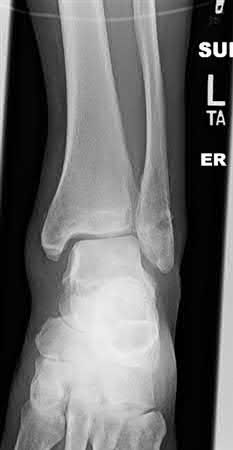

A 25-year-old male sustains an ankle fracture dislocation and undergoes open reduction and internal fixation. He returns to clinic five months following surgery complaining of continued ankle pain and instability with weight bearing. His immediate post-operative AP radiograph is seen in Figure A. Which of the following could have prevented this patient from developing persistent pain?

The patient presents with continued ankle pain and instability following open reduction and internal fixation. The radiograph in figure A demonstrates inadequate restoration of fibular length, likely leading to continued tibiotalar instability.

Illustration A demonstrates fibular malreduction with dislocation of the fibula anterior to the tibial incisura. Illustration B shows a comminuted fibula fracture along with a measurement of length from an intact fibula. The arc from the lateral process of the talus to the peroneal groove of the distal fibula is known as the "dime" sign and should remain unbroken if fibular length has been restored. Illustration C demonstrates the use of a push-pull screw and lamina spreader to regain length intraoperatively for a comminuted fibula fracture.

Chu and Weiner review management of malunions of the distal fibula. The authors state that restoration of fibular length, alignment and rotation leads to reduction of the talus, provides a buttress to talar motion in the setting of an incompetent deltoid, and allows the syndesmotic ligaments to heal at the appropriate tension.

Wikeroy et al conducted a study of patients from a prior prospective, randomized control trial comparing different methods of syndesmotic fixation. There was no significant difference in outcomes between tricortical or quadricortical 3.5mm screw fixation, however worse outcomes were seen with associated posterior malleolar fractures, obesity, a difference in sydesmotic width of 1.5mm or greater, and a CT confirmed tibio-fibular synostosis.

Sinha et al present a simple technique for fibular lengthening in the setting of distal fibula malunion. They found high union rates and improved AOFAS scores at short-term follow up with their technique.